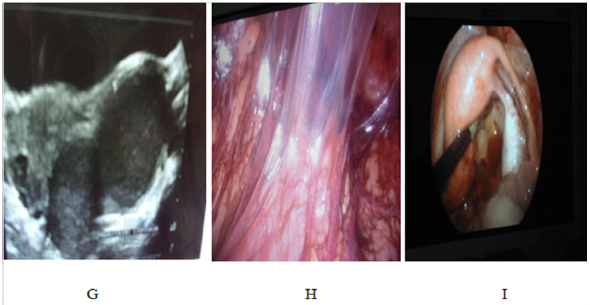

El tercer caso corresponde a adolescente de 14 años de edad, monorreno derecha desde el nacimiento, referida por Nefrología Pediátrica para evaluación ginecológica por presentar dolor pélvico tipo cólico y de presentación cíclica en los últimos tres meses; encontrándose desarrollo mamario /púbico IV (S4 /V4); abdomen doloroso a la palpación profunda en hipogastrio con tumoración visible en hipogastrio; en genitales externos se evidencia doble orificio vaginal permeables y tumoración renitente que protruye sin rebasar el introito vaginal del lado derecho. Al tacto bimanual complementario se palpa polo inferior de tumoración renitente a 4 cm del margen anal correspondiente a segmento vaginal distendido: lo que se confirma a la ecografía abdomino pélvica y renal con los hallazgos de útero didelfo, hematosalpinx, hematocolpometra derecho y agenesia renal derecha; planteándose el diagnóstico de síndrome de OHVIRA.

A las pacientes se les realizaron además de ecografía pélvica, estudios complementarios como RMN y TAC de abdomen y pelvis con contraste, (dos casos); con el fin de establecer las referencias anatómicas de los órganos por contigüidad y la permeabilidad o no de ambos hemisistemas- Por la asociación con alteraciones renales se realizaron otros estudios como: gammagrama renal con DMSA, la cistografía miccional retrograda y / o urografía de eliminación (Fig. 4).

En los tres casos se realizó hemivaginectomia más drenaje de tumor por colección a nivel del segmento vaginal obstructivo y resección del tabique vaginal longitudinal dejando un solo canal vaginal previo abordaje laparoscópico que confirmo presencia de útero didelfo con contenido hemático abundante, libre en cavidad pélvica (hemoperitoneo) y focos de endometriosis, además de hematosalpinx y síndrome adherencial (Fig. 5), permitiendo así por vía laparoscópica corregir las complicaciones asociadas.